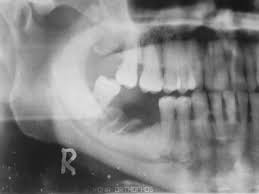

Este estudio contribuye a la escasa pero creciente literatura que asocia un número creciente de fármacos con osteonecrosis de la mandíbula relacionada con la medicación (ONMRM)  y subraya la importancia de considerar todos los fármacos posibles que elevan el riesgo de ONMRM de un paciente. Br J Clin Pharmacol, junio de 2021